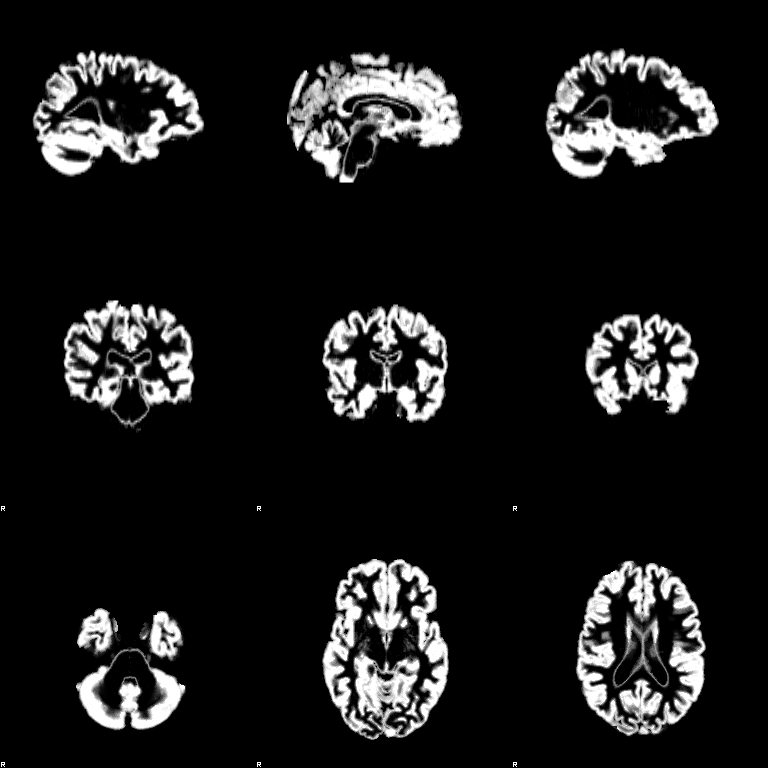

FAST

Set the Input image to be structural_brain (i.e. it is important to have run BET first). Turn on the Partial volume maps optional output images. Press Go. The outputs will be structural_brain_seg, structural_brain_pve_0, structural_brain_pve_1 and structural_brain_pve_2.